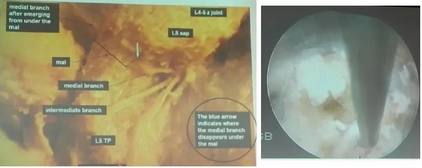

图文结合:单侧双通道内镜技术(UBE)原来没这么难。

通过一个简单的双通道关节镜下腰椎间盘摘除术来介绍一下UBE技术。